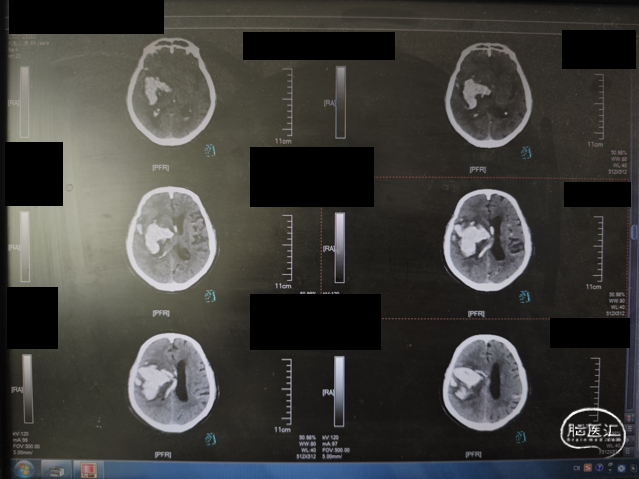

影像所见:右侧脑出血并破入脑液腔系统治疗后复查,右基底节区示团块状高密度影,直径约5.5cm,同恻脑室及双侧脑沟多发高密度铸型改变,中线结构向对侧移位约1cm。

影像提示:右侧脑出血并破入脑液腔;考虑脑疝;建议结合临床。

初步诊断:1. 高血压脑出血(右侧基底节);2. 脑疝;3. 高血压病3级(极高危);4. 吸入性肺炎;5. 冠状动脉粥样硬化性心脏病;6. 脑梗死后遗症;7. 2型糖尿病?

术前CT